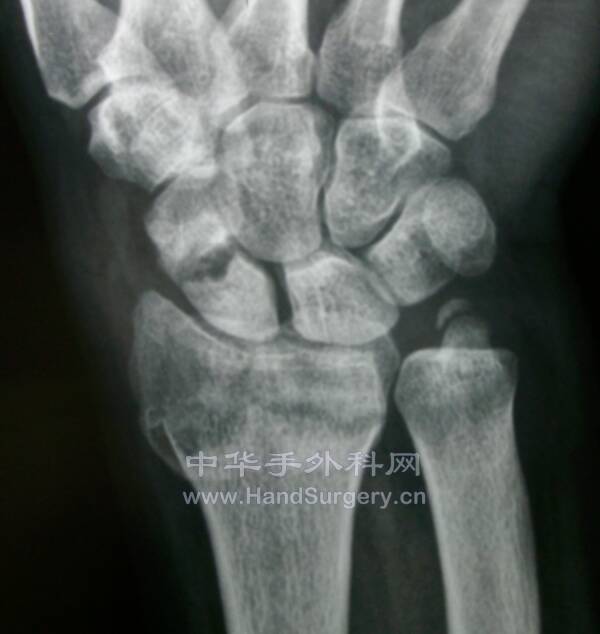

桡骨远端骨折,远端粉碎或太短,不能接受钢板远端钉排

克氏针+外固定支架是绝佳选择

这里就是其中一个典型病例

桡骨远端骨折C3型合并舟骨骨折